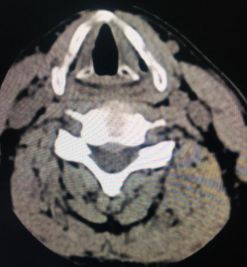

全新日本进口佳能金刚螺旋CT

该新设备功能先进,有平扫、三维重建、X线计算机体层成像等功能,能对人的头部、颈部、胸腔、四肢、盆腔等多个部位进行扫描成像。

颈椎椎间盘突出

硬膜外血肿

腰椎椎间盘膨出伴双侧神经根受压

右侧上颌窦炎

原发性肝癌伴骨转移

该设备自运行以来,发现并确诊不少疾病:颈椎椎间盘突出、 腰椎椎间盘膨出伴双侧神经根受压、硬膜外血肿、右侧上颌窦炎、右侧筛窦炎、双肺感染伴双侧胸腔积液、心包积液、右侧胸腔包裹性积液、原发性肝癌伴骨转移等疾病。